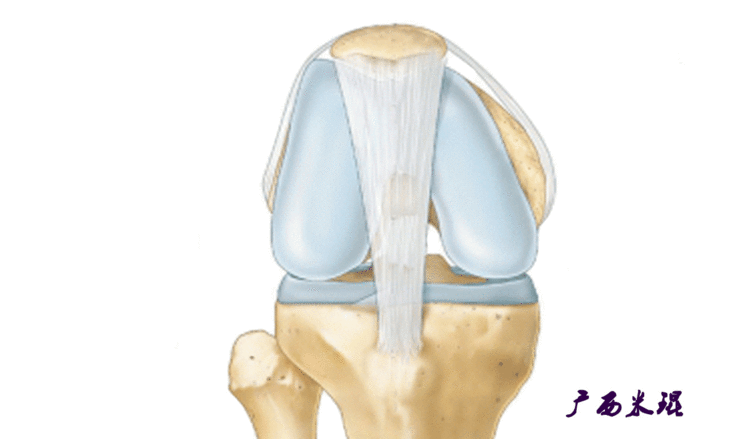

说到髌骨脱位,首先就要了解髌骨,髌骨是人体最大的籽骨,倒三角状位于膝关节前方,它的上缘与股四头肌腱相连,下缘通过髌韧带止于胫骨结节上,两侧为股四头肌扩张部,髌骨后方的凸面为光滑的关节面,与股骨下端内外髁之间的滑车凹面关节面形成关节。尽管股四头肌中的股直肌、股中间肌、股外侧肌的作用方向与髌韧带不在一条直线上,髌骨有向外突出的倾向,但因股内侧肌有向内上方牵拉作用力而使髌骨维持在正常位置。

髌骨脱位绝大部分是向外侧脱位,脱位后,髌股关节内侧的稳定结构,包括髌股关节内侧支持带、股内侧肌、内侧髌股韧带均被撕裂,导致膝关节腔内积肿,在髌骨脱位以及自行复位的过程中,髌骨内侧面与股骨髁外侧面撞击,会引起软骨损伤或骨软骨骨折,所以,千万不要把髌骨脱位当作成一个简单的疾病。

从0到30°限制髌骨外侧位移最重要的是MPFL(内侧髌股韧带),文献报道认为导致髌股关节不稳的主要原因是内侧髌股韧带损伤,而在限制髌骨向外移位过程中,内侧髌股韧带提供约60%的力量,所以重建MPFL是治疗复发性髌骨脱位的有效方法。即使这样,MPFL重建也不是万能的,寄希望于MPFL重建解决所有的髌骨脱位肯定是不现实的,MPFL重建有着严格的适应症和技术要求,对于骨骺未闭合者,股骨端的骨隧道必须避开骺板,以免影响骨骼的生长。